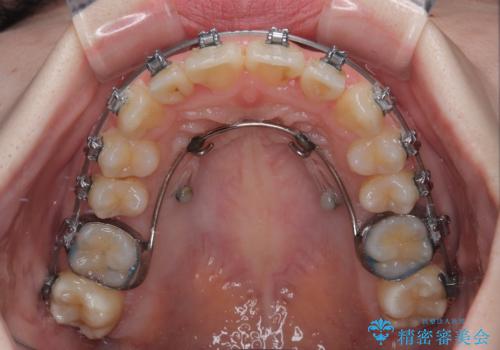

- メタルブラケット

マウスピースでもワイヤー装置でも対応可能でしたが、右側の咬み合わせが上顎がやや前方に位置していることから、補助装置を使用することが推奨されました。

自己管理の煩わしさを気にして、補助装置併用によるワイヤー装置での矯正治療を行うこととしました。

右上と左下の第一大臼歯2本が周辺の歯と比べて位置がずれていたため、ゴムかけやワイヤーに曲げを入れることで移動を試みましたが、どうよら癒着をしており、移動困難と判断されました。